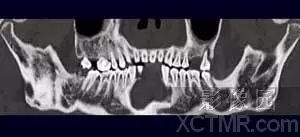

② 曲面重建(CPR):是MPR的一种特殊方法,适合于人体一些曲面结构器官的显示,如:颌骨、迂曲的血管、支气管等。曲面重建图象的客观性颌准确性和操作者点画线的精确性有很密切的关系。